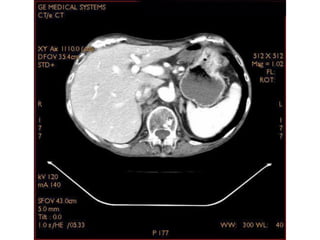

Imagem de corte axial com

janela para tecido ósseo